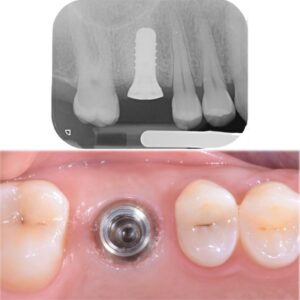

Inserimento dell’impianto dentale

L’intervento di inserimento dell’impianto avviene in anestesia locale e, nella maggior parte dei casi, non è doloroso. L’impianto viene posizionato all’interno dell’osso e successivamente coperto dalla gengiva per permettere il processo di osteointegrazione, cioè l’unione stabile tra osso e impianto.

Osteointegrazione e tempi di guarigione

L’osteointegrazione richiede generalmente da 2 a 6 mesi, a seconda della zona trattata e delle condizioni individuali del paziente. Durante questo periodo l’impianto si stabilizza e diventa una base solida per il dente definitivo.

Applicazione della protesi definitiva

Una volta completata la guarigione, sull’impianto viene fissata la corona dentale definitiva, progettata per integrarsi armoniosamente con i denti naturali per forma, colore e funzione.